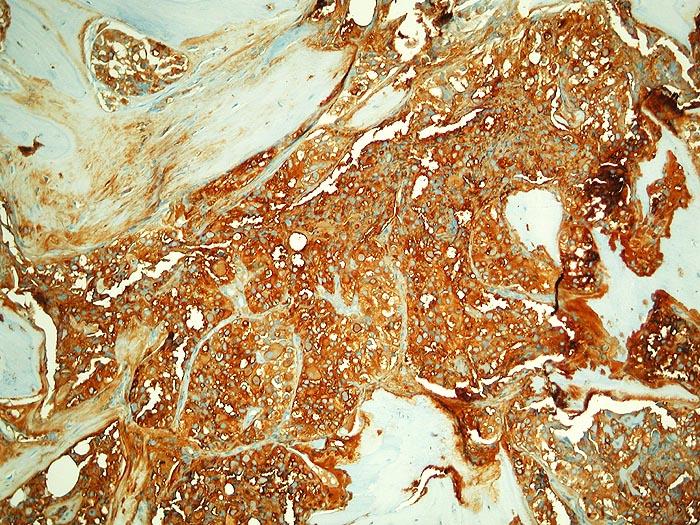

PathoPic – image database / PathoPic ID 2787 - Metastase follikuläres Schilddrüsenkarzinom

Metastase follikuläres Schilddrüsenkarzinom

maligner Tumor

Knochen, Becken

Die malignen Zellen reagieren stark mit Thyreoglobulin.

Die Tumorzellen reagieren positiv mit Thyreoglobulin sowie mit dem nukleären Transkriptionsfaktor TTF-1

Kein bekanntes Schilddrüsenkarzinom. Vor 30 Jahren Adenokarzinom des Kolons.

Histologie

Immunhistochemie

Thyreoglobulin